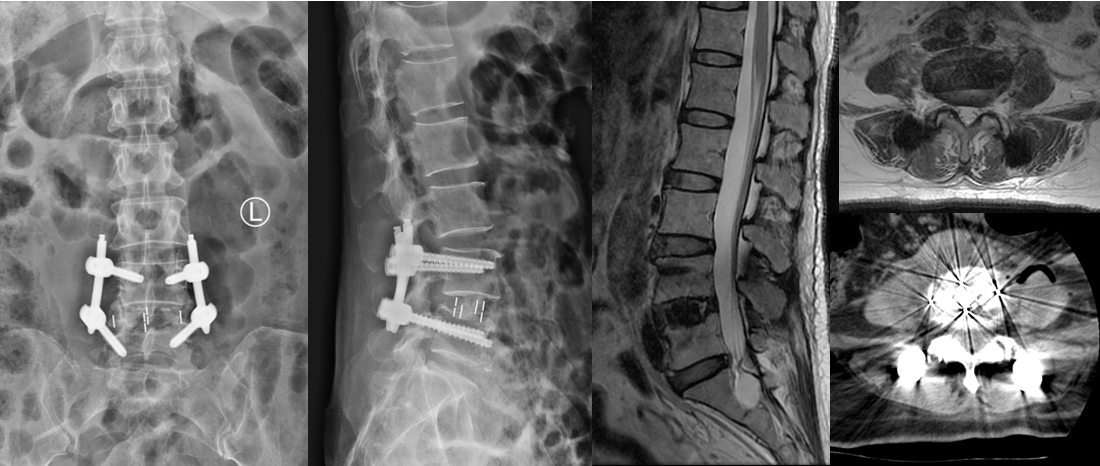

第二例患者男性,67岁,患者因“腰痛并右下肢放射痛1年余,加重1月”入院,发病以来反复保守治疗,未好转,1月前症状加重,间歇性跛行,行走100米后因疼痛无法继续行走。入院后经术前讨论、评估,制定治疗方案,行OLIF手术。次日患者下地活动,下肢症状消失,疗效满意。

术前影像

术后复查